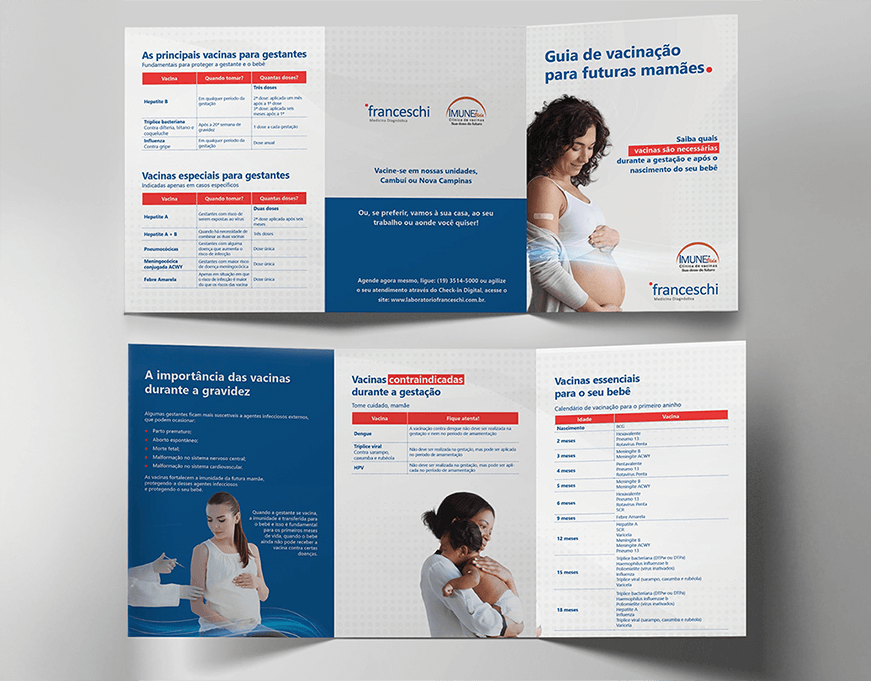

Focados no mercado B2C, atuamos na criação de marcas e campanhas on e off.

Catálogos comerciais

Materiais gráficos

Embalagens